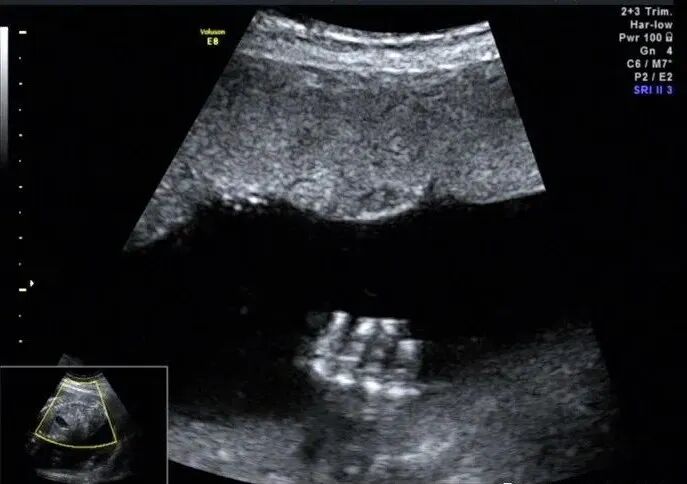

12周后胎儿四肢就可以完整显示,NT筛查时也建议对胎儿四肢进行观察。对于肢体检查最好采用连续追踪扫查法,尽量一次完成,如果由于体位原因看了一半,没有完成,最好在下次观察肢体时依然采用连续不间断扫查把整个肢体检查完毕。扫查时包括关节、肢体姿势、骨骼及皮肤。扫查到手脚后旋转探头打到远端指骨(趾骨)末端,观察手指(脚趾)个数、形态,有无手指(脚趾)缺失、多指(趾)或重叠指等,具体方法如下图

膝关节及踝关节情况